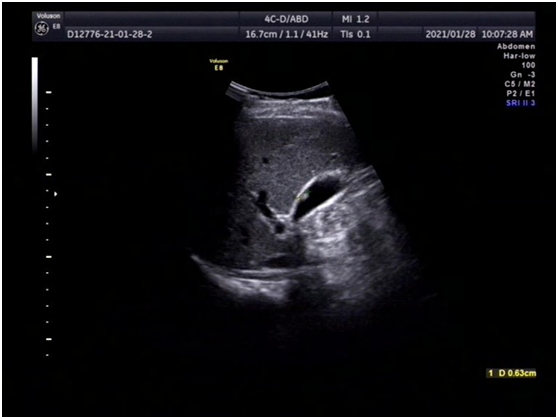

· 胆囊上长"肉肉",怎么办? ( ) 张先生, 34岁,近来一直感觉右上腹不适,经b超检查提示胆囊息肉样病变,已有1厘米大小,于是在医生的建议下做了胆囊切除术。术后,切除的胆囊病理检查报告提示慢性胆囊炎伴腺肌瘤样增生。 张先生的胆囊到底怎么了? 首先,我们说说胆囊息肉样0805 胆囊多发息肉怎么办呢? 0702 多发性胆囊息肉怎么办? 948; · 长了胆囊息肉怎么办? 近年来,人们在进行常规健康体检时,越来越多地被检查出胆囊"异常"——胆囊息肉。 胆囊上长出来的小息肉虽对日常生活不会有太大影响,但却让不少患者心理蒙上了一层"癌变"的阴影。 在临床上,针对"胆囊息肉"的治疗分为两种,一种只需观察治疗,定期复查即可,另一种则建议尽早手术切除,以防癌变。 那么,长了胆囊息肉

胆囊息肉怎么办- · 胆囊息肉、胆囊结石严重吗? 胆囊息肉指胆囊内生长出来的息肉样的病变,其中大多数小于10cm的胆囊息肉是良性的疾病,恶变的几率较低,不必过分忧虑,只需要定期复查即可。 但是大于10cm以上的则有癌变的可能,此时就需要提高警惕必要时手术治疗,以避免贻误病情。 胆囊结石是胆道系统最常见的一类疾病,结石本身对身体没有影响,但其可能引起胆囊炎 · 胆囊上长"肉肉",怎么办? 21 04/17 分享 评论 复旦大学附属华山医院 aa 张先生,34岁,近来一直感觉右上腹不适,经b超检查提示胆囊息肉样病变,已有1厘米大小,于是在医生的建议下做了胆囊切除术。术后,切除的胆囊病理检查报告提示慢性胆囊炎伴腺肌瘤样增生。 张先生的胆囊到底怎么